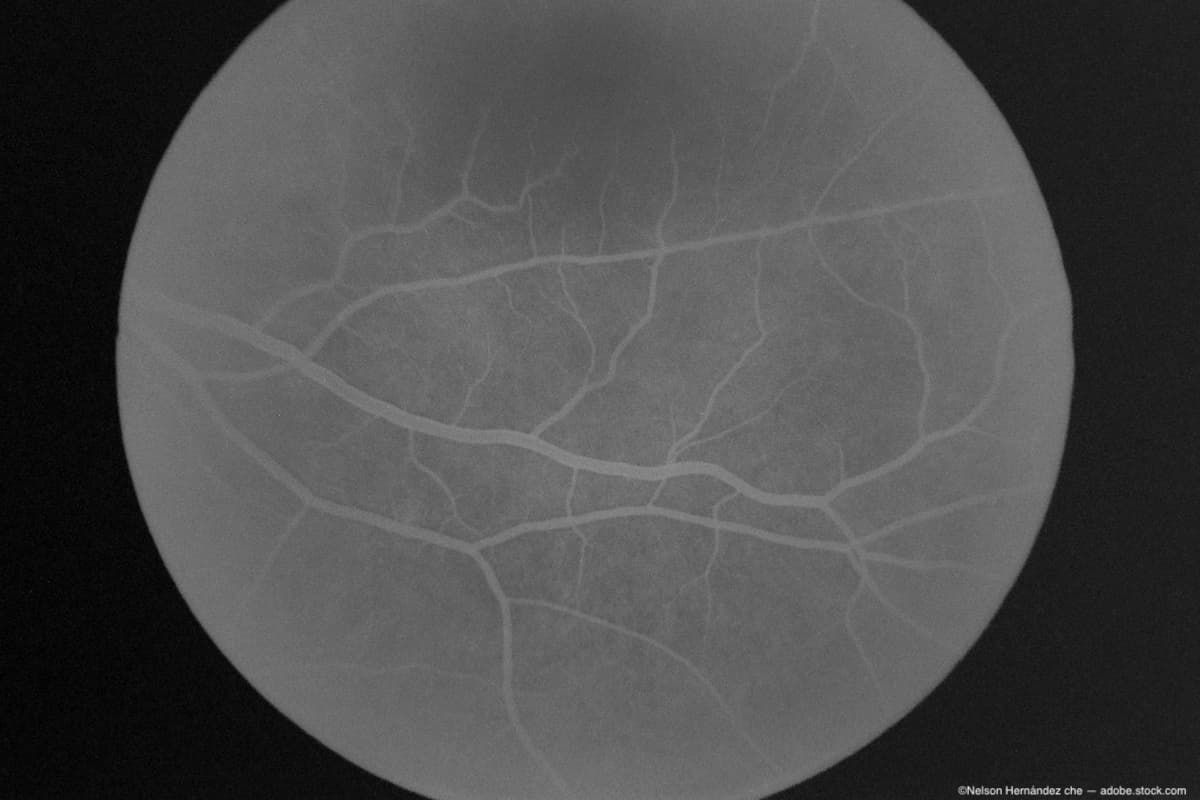

Eye drops developed by Columbia University researchers could prove to be a more effective and comfortable therapy for retinal vein occlusion (RVO).